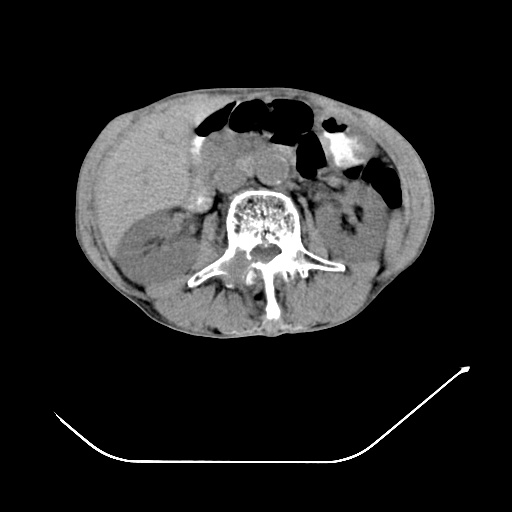

以下是引用zsl6918在2008-8-25 21:55:00的发言:[br]符合右肺周围性肺癌并肺内转移,左肺结核球。双肺肺气肿。腰椎附件转移。

以下是引用随光逐影在2008-8-25 22:03:00的发言:[br]1)考虑右肺下叶周围性肺癌并肺内转移,腰椎附件转移。2)左上肺结核(结核球形成)。3)双肺肺气肿(多发肺大泡形成)。4)双肺门区及纵隔内多发淋巴结钙化。